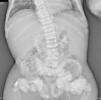

The chest X-ray (Fig. 1) demonstrated nodular periarticular calcification in the shoulders, dorsal vertebral osteosclerosis and vertebral collapse of thoracic vertebrae 5 and 6, with sequelae of rib fractures and a fracture of the right humerus. An abdominal X-ray (Fig. 2) showed bilateral nephrocalcinosis, vertebral osteosclerosis which also affected pelvic bones, bilateral nodular calcifications and a subtrochanteric fracture.